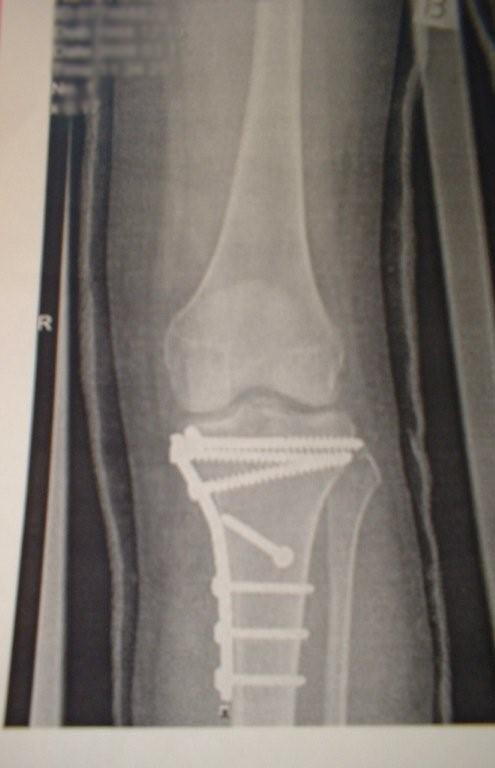

Nekem iden márciusban eltörött a sípcsontom condylusa,a porc es az összes szalag.Izületbe hatoló törés

A keresztszalagot eltávolították,az oldalsókat varrták.A sípcsont izületi végét csontbankból vett csonttal rekonstruálták és oldalról lemezzel rögzítették.6 hete brace rögzítővel járok.Még nem terhelhetem.Viszont hajlítanom kellene,de nem megy.Gyógytornász segítségével próbálom de 45 foknál jobban nem tudom.Nagyon el vagyok keseredve.A gyógytornász szerint idővel menni fog.Ki kell nyújtani a szalagokat.Én most úgy érzem nem megy.Az izmaim jócskán elsorvadtak.Lesz ebből valaha járás?Tudtok nekem tapadztalatokat mondani?

Az alábbi kép balesete ugyan nem a pályán történt, hanem egy közlekedési balesetben, azóta srác teljesen felépült, és újra tökéletesen síel...

Kitartást és gyógyulást mindenkinek!

68407289fa894adbcafaea09743a5d7c.jpg

Egy pár csavar eltéréssel, akár lehetne az én lábam is...

Képek  1 (2).jpg  55 KB  letöltve 2708 alkalommal

Remélem ez a csúnya sérülés nem tántorított el a síeléstől. Szerintem jobban jártál a töréssel, mint egy keresztszalag szakadással. Bár a felvételeket nézve, raktak be bőven "vasat".